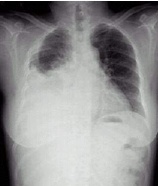

| 病史:女性,76歲,胸悶伴呼吸困難6天,不能平臥1天。診斷: |

| ○右側(cè)胸腔積液 | |

| ○右下肺不張 | |

| ○右下胸膜肥厚 | |

| ○大葉肺炎 | |

| ○氣胸 |